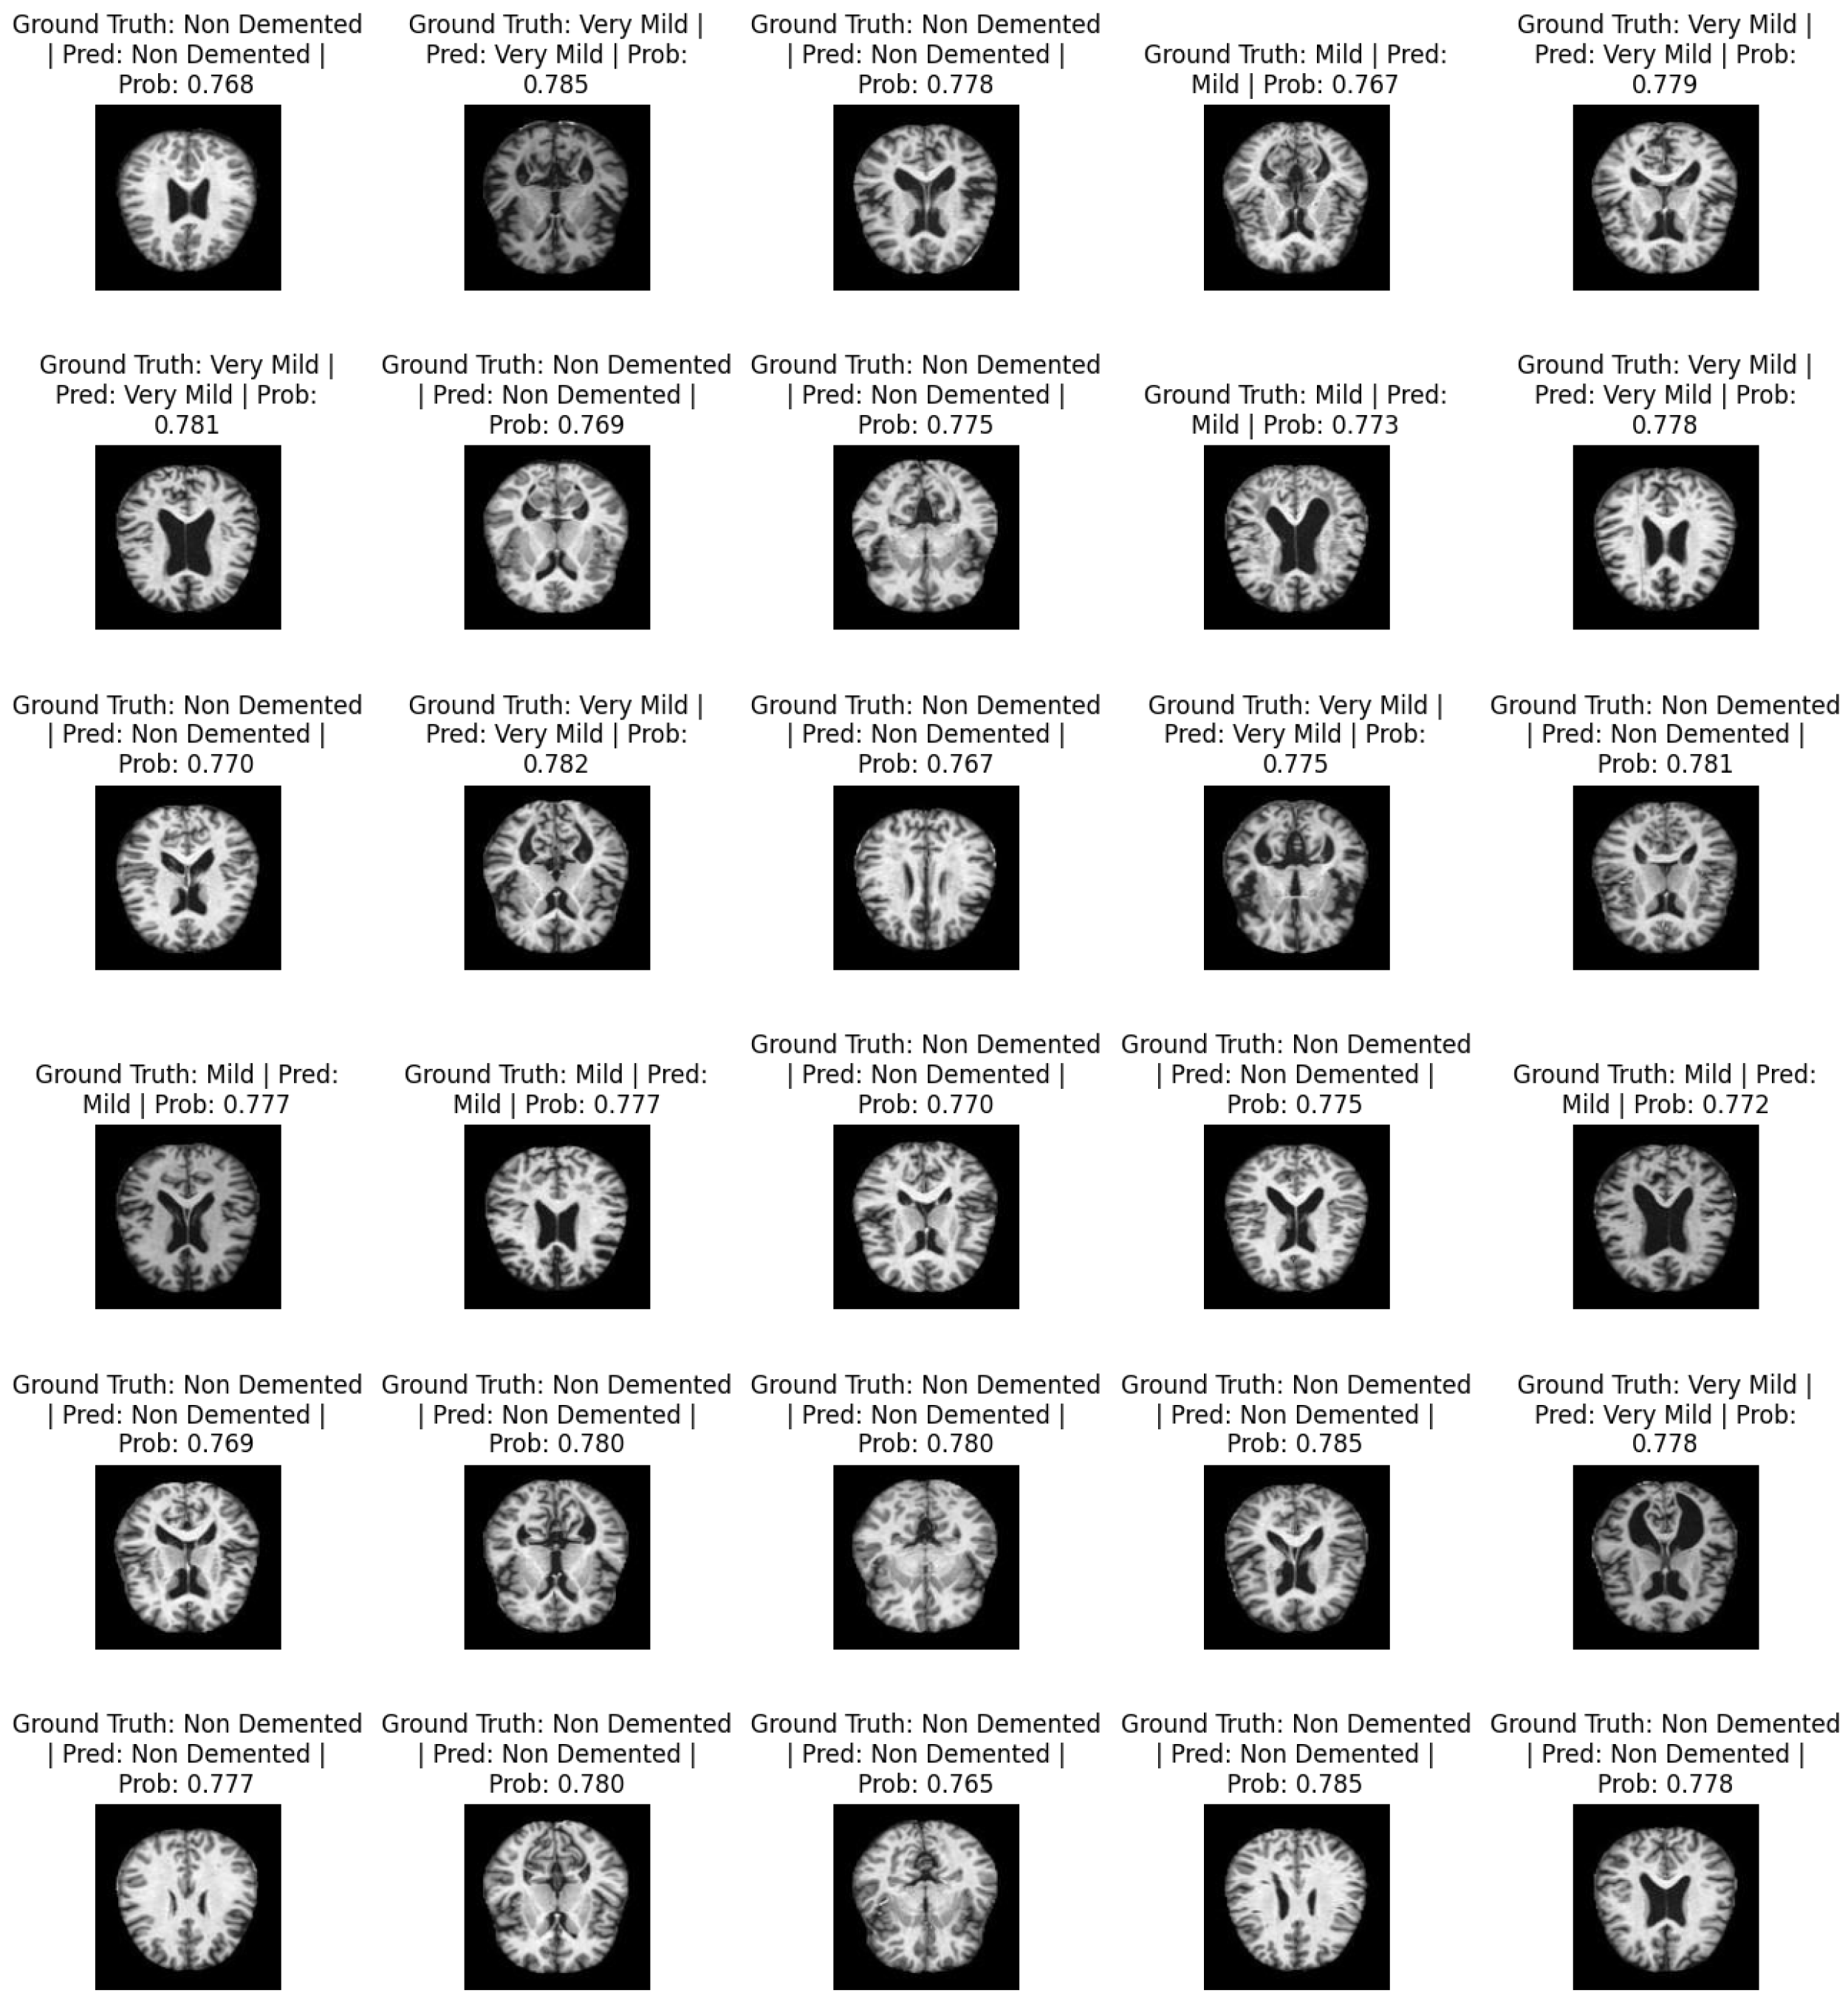

Figure 4 shows a sample of predicted images. It contains information about the actual labels and predicted labels: i.e., ground truth and prediction. For each image, the classification probabilities ranging from 0 and 1 show the probability of the image being classified as one of the respective classes. The total number of classes is non-demented, mild, moderate demented, and very mild.

Figure 4. Predicted AD classification.